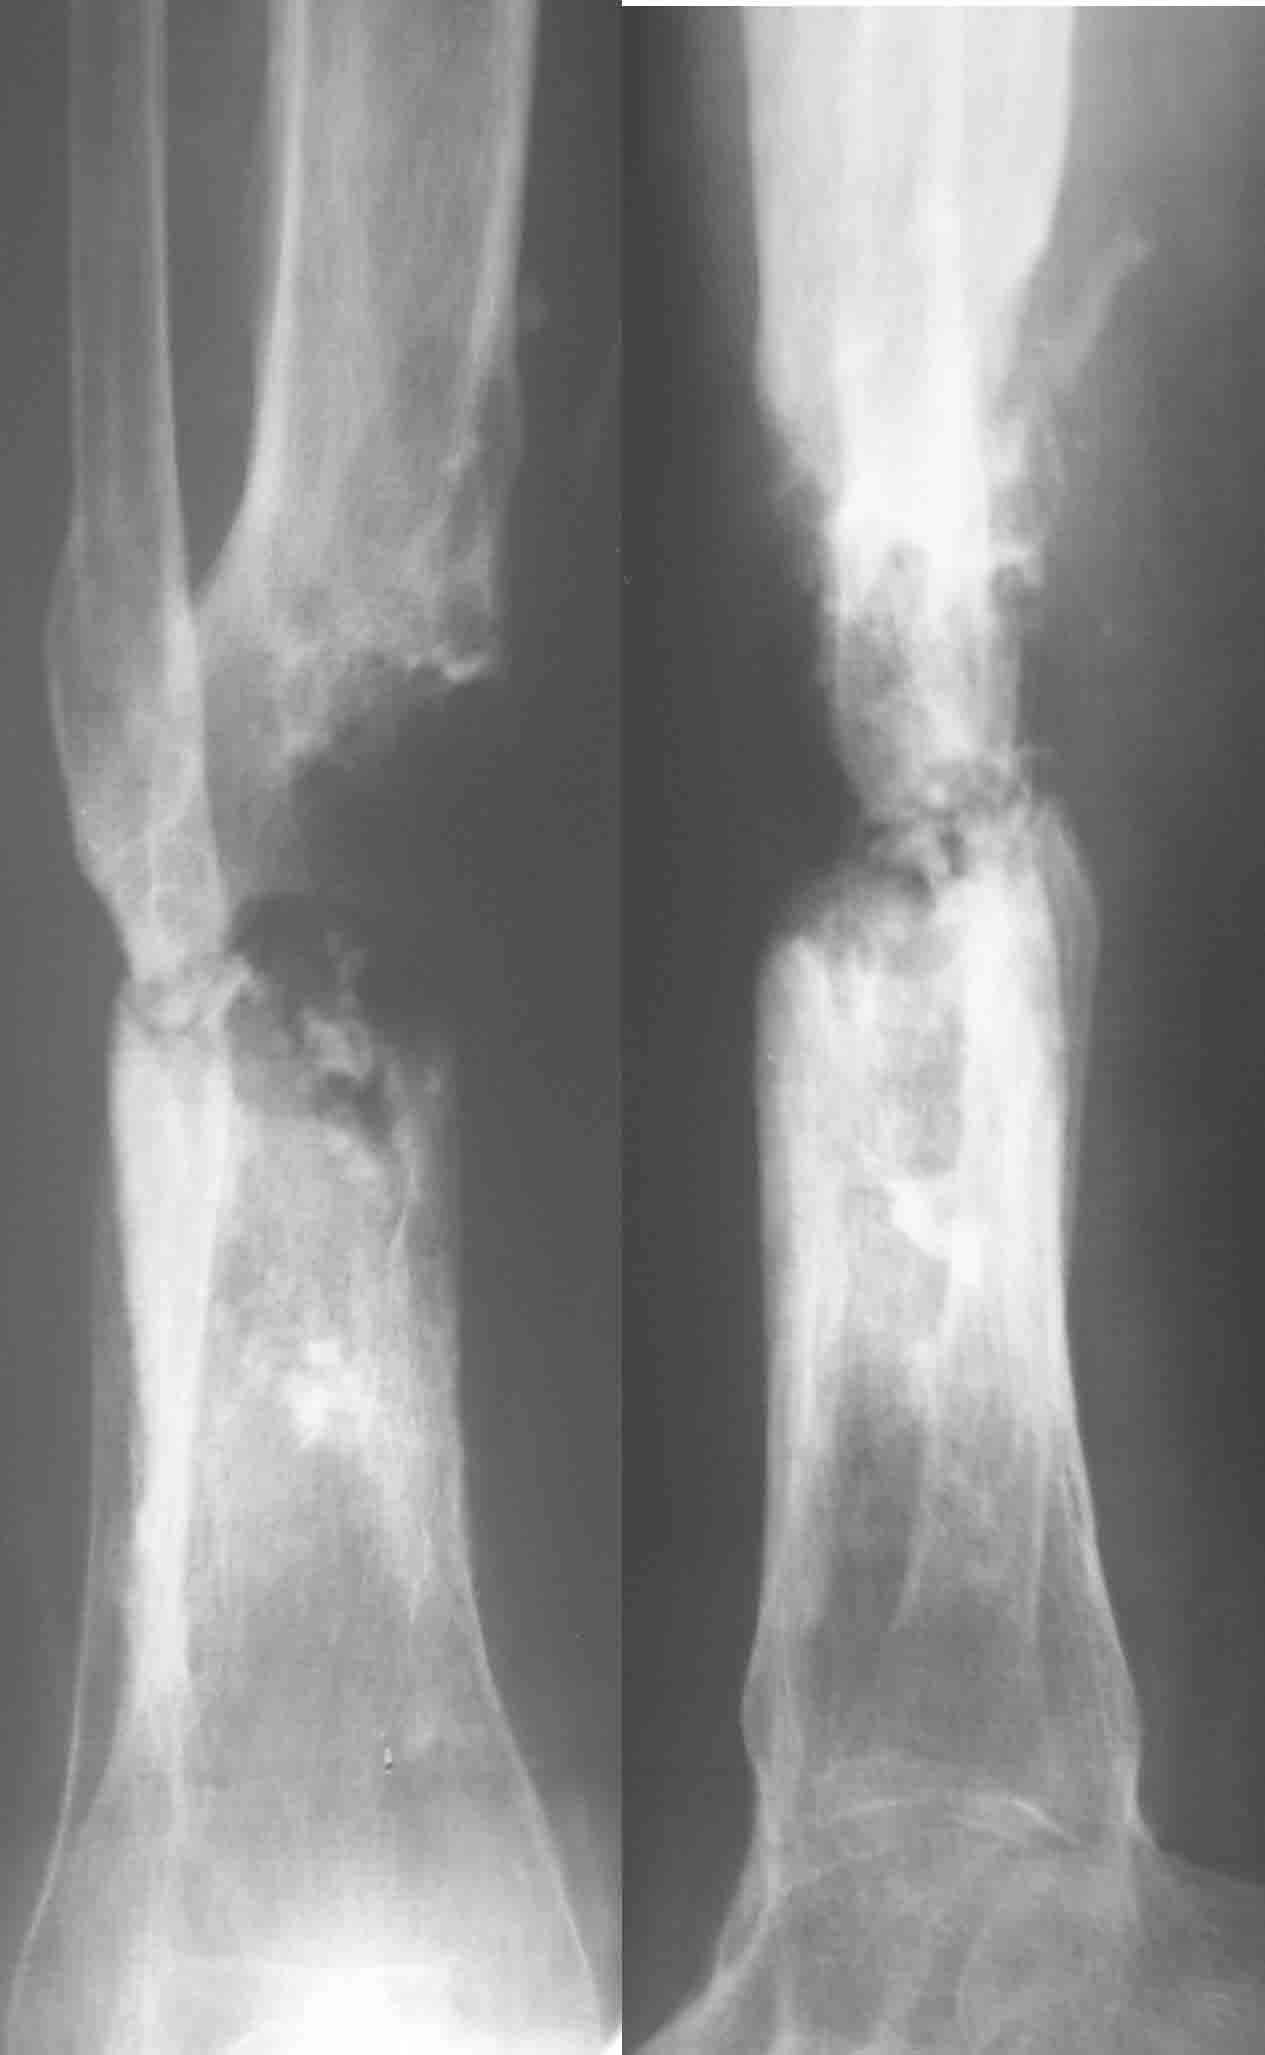

Кратко: мужчина за 60 лет получил травму 28 лет назад (переехало автобусом). Оперировался десятки раз, в итоге с очередным патологическим переломом, хронической язвой и гипсовой лонгетой попал ко мне... Объективно - остеомиелит, инфицированный ложный сустав (или как его назвать), флегмона по наружной поверхности

голени, укорочение около 5 см.

На операции резекция 8 см, внешний остеосинтез,одновременное сближение примерно на 4 см, а затем постепенное сближение до полного контакта в течение 3 недель. Рана с патологически измененными краями, имевшая на операции размеры примерно 4-5 на 10-12 см закрылась самостоятельно в течение примерно 2-х мес. Ну не самостоятельно, конечно, а с нашей помощью, но без пластики.

Сейчас в аппарате вытянул около 6 см в верхней трети.